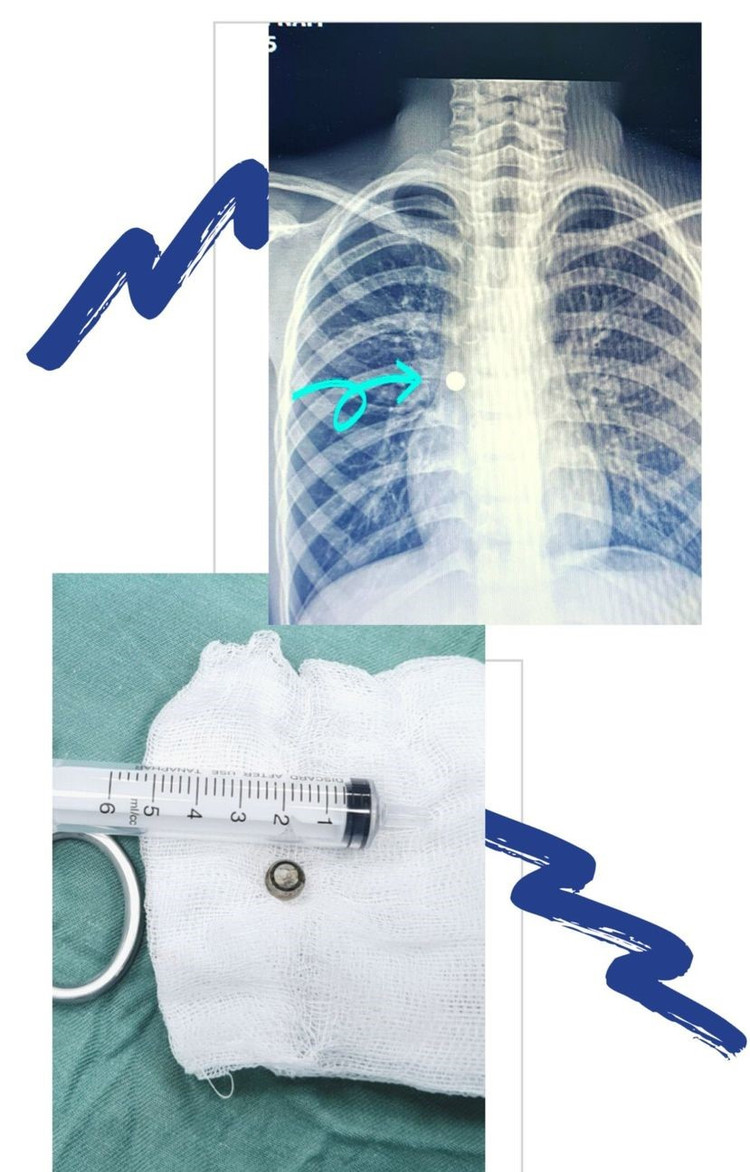

Bệnh nhi nhanh chóng được chuyển lên khoa Gây mê để tiến hành lấy dị vật. Khẩu kính phế quản của trẻ lại nhỏ nên rất khó khăn để lấy dị vật. Sau rất nhiều nỗ lực, các bác sĩ đã nội soi gắp thành công dị vật là một cục pin nhỏ (dạng pin cúc áo trong các món đồ chơi của trẻ) đường kính hơn 1 cm, cứu sống bệnh nhi kịp thời.

Sau thủ thuật, sức khoẻ bệnh nhi ổn định. Kiểm tra sau khi lấy dị vật, bác sĩ đánh giá kết quả trẻ vẫn bị dị vật gây tổn thương niêm mạc phế quản, trẻ được theo dõi kỹ tình trạng phổi để tránh biến chứng viêm thủng khí quản.